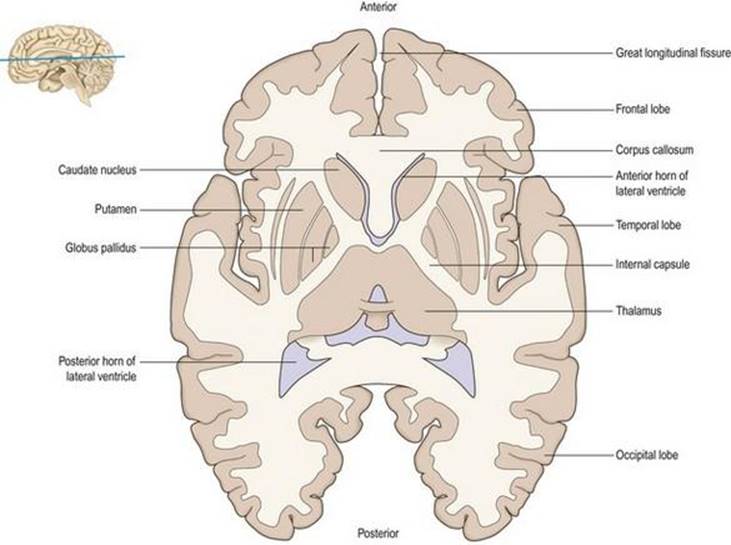

نیمکره مغز تا حد زیادی بزرگترین بخش مغز است. مانند مخچه، از یک لایه بیرونی یا قشر از ماده خاکستری و یک توده داخلی از ماده سفید تشکیل شده است (شکل ۱.۲۰، ۱.۲۱). علاوه بر این، تا حدی در داخل ماده سفید زیر قشری چندین توده بزرگ از اجسام سلولی قرار دارند که در مجموع به آنها عقدههای پایه میگویند (شکلهای ۱.۵، ۱.۲۰، ۱.۲۱). دو نیمکره مغزی توسط یک شکاف خط میانی عمیق، شکاف طولی بزرگ (شکل ۱.۲۰) از هم جدا میشوند که فالکس سربری (falx cerebri) را در خود جای میدهد. در اعماق شکاف جسم پینه ای قرار دارد (شکل ۱.12A، ۱.۲۰)، ورقه بزرگی از رشتههای عصبی متقاطع (فیبرهای کمسیورال) که نواحی متناظر دو قشر مغز را به هم متصل میکند.

شکل ۱.۲۰ برش تاج از نیمکره مغزی

شکل ۱.۲۰ برش تاج از نیمکره مغزی

شکل ۱.۲۱ برش افقی از نیمکره مغزی.

شکل ۱.۲۱ برش افقی از نیمکره مغزی.

ساختار اصلی نیمکره مغزی یک گوشته بیرونی از ماده خاکستری، قشر مغز است که در زیر آن توده بزرگ و پیچیده ای از ماده سفید قرار دارد که از رشتههای عصبی به سمت و سوی قشر مغز تشکیل شده است (شکلهای ۱.۲۰، ۱.۲۱، ۱.۲۳ ).

الیاف آوران و وابران قشری که بین قشر مغز و ساختارهای زیر قشری مانند جسم مخطط، تالاموس، ساقه مغز و نخاع عبور میکنند در یک الگوی تشعشعی مشخص قرار گرفتهاند، تاج رادیاتا، که به پیچشهای سطح قشر مغز میرسد. شکل ۱.۲۳). الیاف در عمق بیشتری در داخل نیمکره در یک صفحه متراکم از ماده سفید متمرکز میشوند که به عنوان کپسول داخلی شناخته میشود (شکلهای ۱.۲۰، ۱.۲۱، ۱.۲۳).

در اعماق نیمکره، هم داخلی و هم جانبی کپسول داخلی، تودههای اضافی از ماده خاکستری وجود دارد که معمولاً در مجموع به آن عقدههای بازال میگویند. بزرگترین آنها جسم مخطط است که از هسته دمی، پوتامن و گلوبوس پالیدوس تشکیل شده است (شکل ۱.۲۰، ۱.۲۱). هسته دمیدر تمام وسعت خود در دیواره بطن جانبی قرار دارد و مانند بطن C شکل است. عقدههای قاعده ای به کنترل تون عضلانی، وضعیت و حرکت مربوط میشوند (فصل ۱۴).